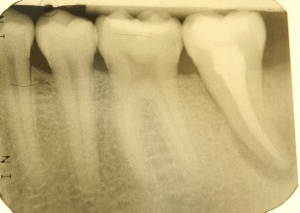

Diagnostische Parameter für die Beurteilung der dentalen und der periimplantären Zustände sind die Plaqueakkumulation, die Sondierungstiefen des Zahnes und des Implantates, Bluten auf Sondierung, Suppuration und der radiographische Knochenverlust (Salvi & Lang 2004). Unabdingbar ist im Minimum eine Sechspunktmessung (Sondiertiefen und klinischer Attachmentlevel). Immer wieder hört man von der Befürchtung, dass durch ein Sondieren des Implantates dieses geschädigt wird. In einer histomorphometrischen Studie an Hunden haben Etter et al. (2002) die Heilung des periimplantären Weichgewebes nach standardisiert klinischem Sondieren untersucht. Die Heilung des Epithelansatzes nach Sondierung des gesunden periimplantären Gewebes ist nach fünf Tagen abgeschlossen. Erfahrungsgemäß ist bei besonders aufmerksamem und vorsichtigem Sondieren ein äußerst geringes Verletzungsrisiko gegeben. Auch diese Techniken können in einem Praktikum bei einem Parodontologen aufgefrischt werden.

Im Rahmen einer solchen Nachuntersuchung werden neben der Plaqueakkumulation die klinischen Parameter Sondiertiefe und klinischer Attachmentlevel (6-fach je Zahn / Implantat), Bluten nach Sondieren (BnS), Suppuration und gegebenenfalls der radiographische Knochenverlust (Salvi & Lang 2004) erfasst.